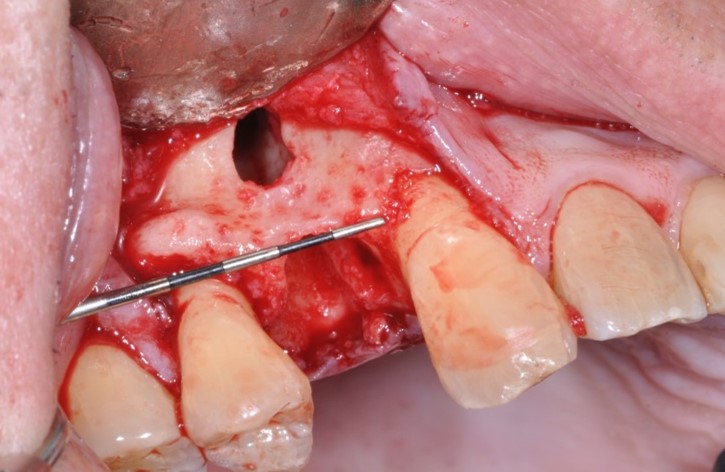

Barrier membranes exclude surrounding, faster growing epithelium cells from populating an extraction socket allowing bone remodeling, deposition, and maturation. The addition of bone augmentation material acts as an osteo-inductive and/or osteo-conductive scaffold. Angiogenesis of new blood vessels into the site promote introduction of osteoprogenitor cells. These osteoblasts and osteoclasts utilize the mineral components of the graft material to deposit organized, osseous architecture over a period of three to six months. Angiogenesis can be enhanced with decortication of the existing bony architecture allowing enhanced bulk and density, a principle called “regional acceleratory phenomenon”.

Figure Legend: A 38 y.o. white male patient presented with a chief complaint of persisting pain in the upper right area, ( tooth #5) for days. Diagnosis was endodontic lesion with a hopeless prognosis (Figure 1, 2). The tooth was extracted and Regional Acceleratory Phenomena performed (Figure 3), grafted with Allograft and Resorbable membrane (Figure 4 &5) employed for Guided Bone Regeneration (GBR) and sutured (Figure 6). Four months post Extraction and Ridge Preservation surgery (Figures 7 and 8, Implant was placed (Figure 9) to be restored after osseointegration period.